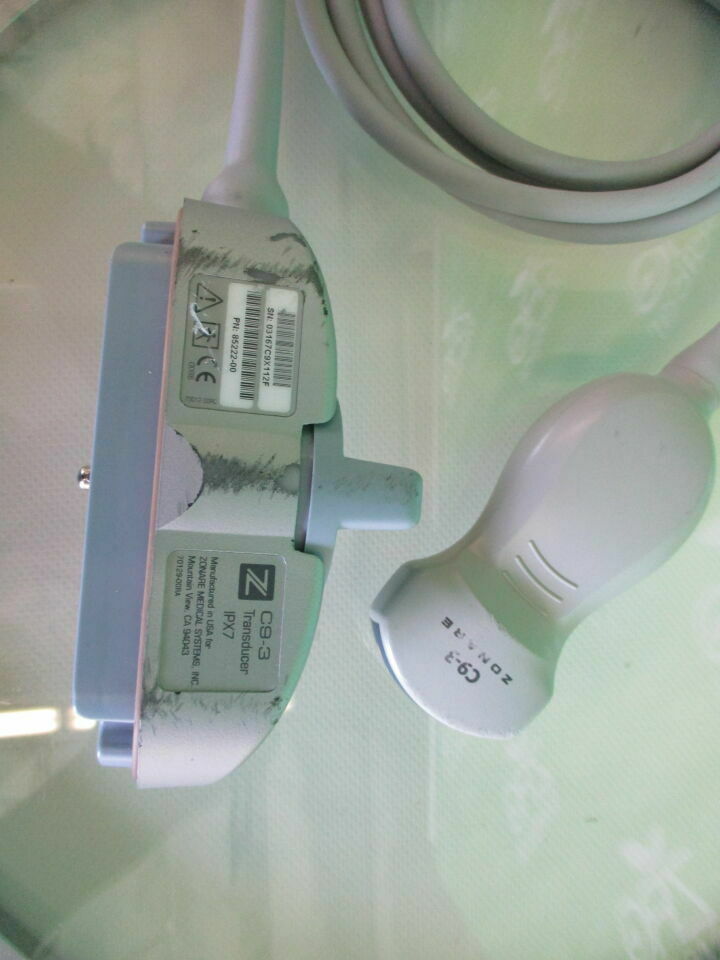

ZONARE C9-3 Ultrasound Transducer

Sale price$ 1,045.50

Regular price$ 1,275.00